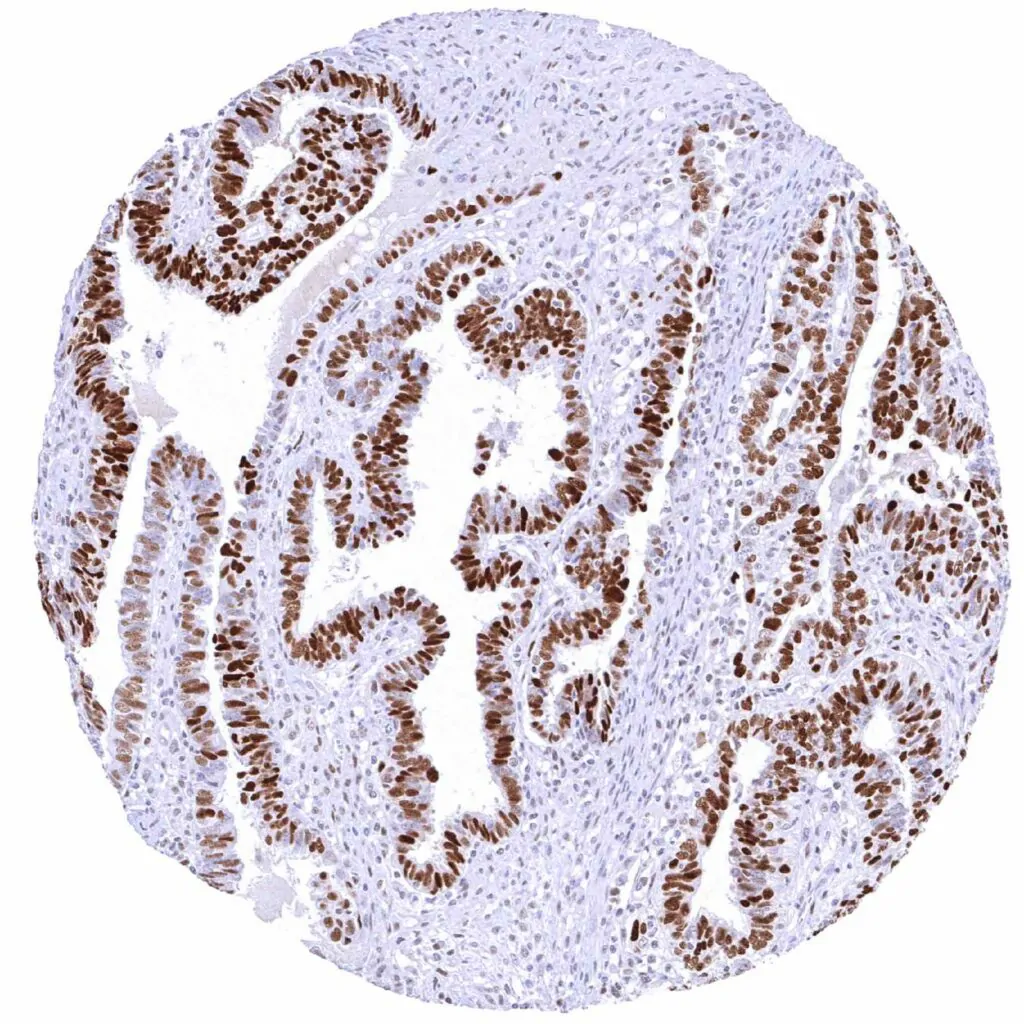

Colon – Colorectal adenocarcinoma with moderate Cyclin E1 positivity of most tumor cells